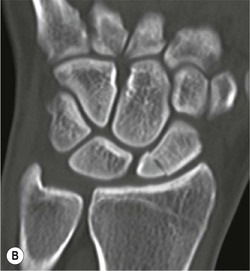

The scapholunate ligament is most frequently involved. Radiographs may show scapholunate diastasis (>3 mm). The lunate demonstrates dorsal rotation on lateral views and volar rotation of the scaphoid. This results in an increase in the scapholunate angle (>60°) known as dorsal intercalated segment instability (DISI) (Fig. 46-27). A DISI deformity of the carpus may also be associated with fractures of the scaphoid.

Abnormal communication between the radiocarpal and midcarpal joints may be seen on arthrography (Fig. 46-28), which is usually combined with MRI or CT16 (Figs. 46-29 and 46-30). However, direct visualisation of the ligaments is possible with conventional MRI. The most important features to describe that help determine management include the following: